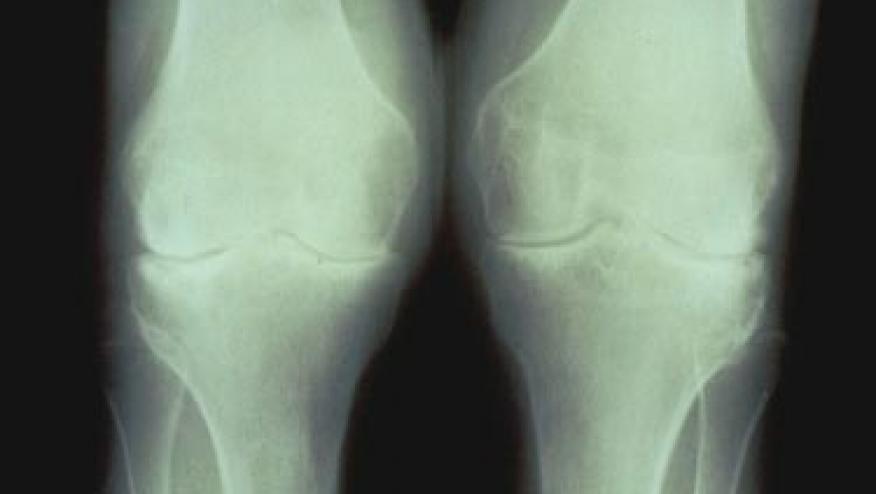

The average American today is twice as likely to be diagnosed with knee osteoarthritis as in the years before World War II, Harvard scientists say. And the reasons are less clear than you might think.

Based on a study of more than 2,000 skeletons from cadaveric and archaeological collections across the United States, a Harvard report is the first to definitively show that knee osteoarthritis prevalence has dramatically increased in recent decades.

Osteoarthritis affects an estimated one-third of Americans over age 60, and is implicated in more disability than almost any other musculoskeletal disorder.